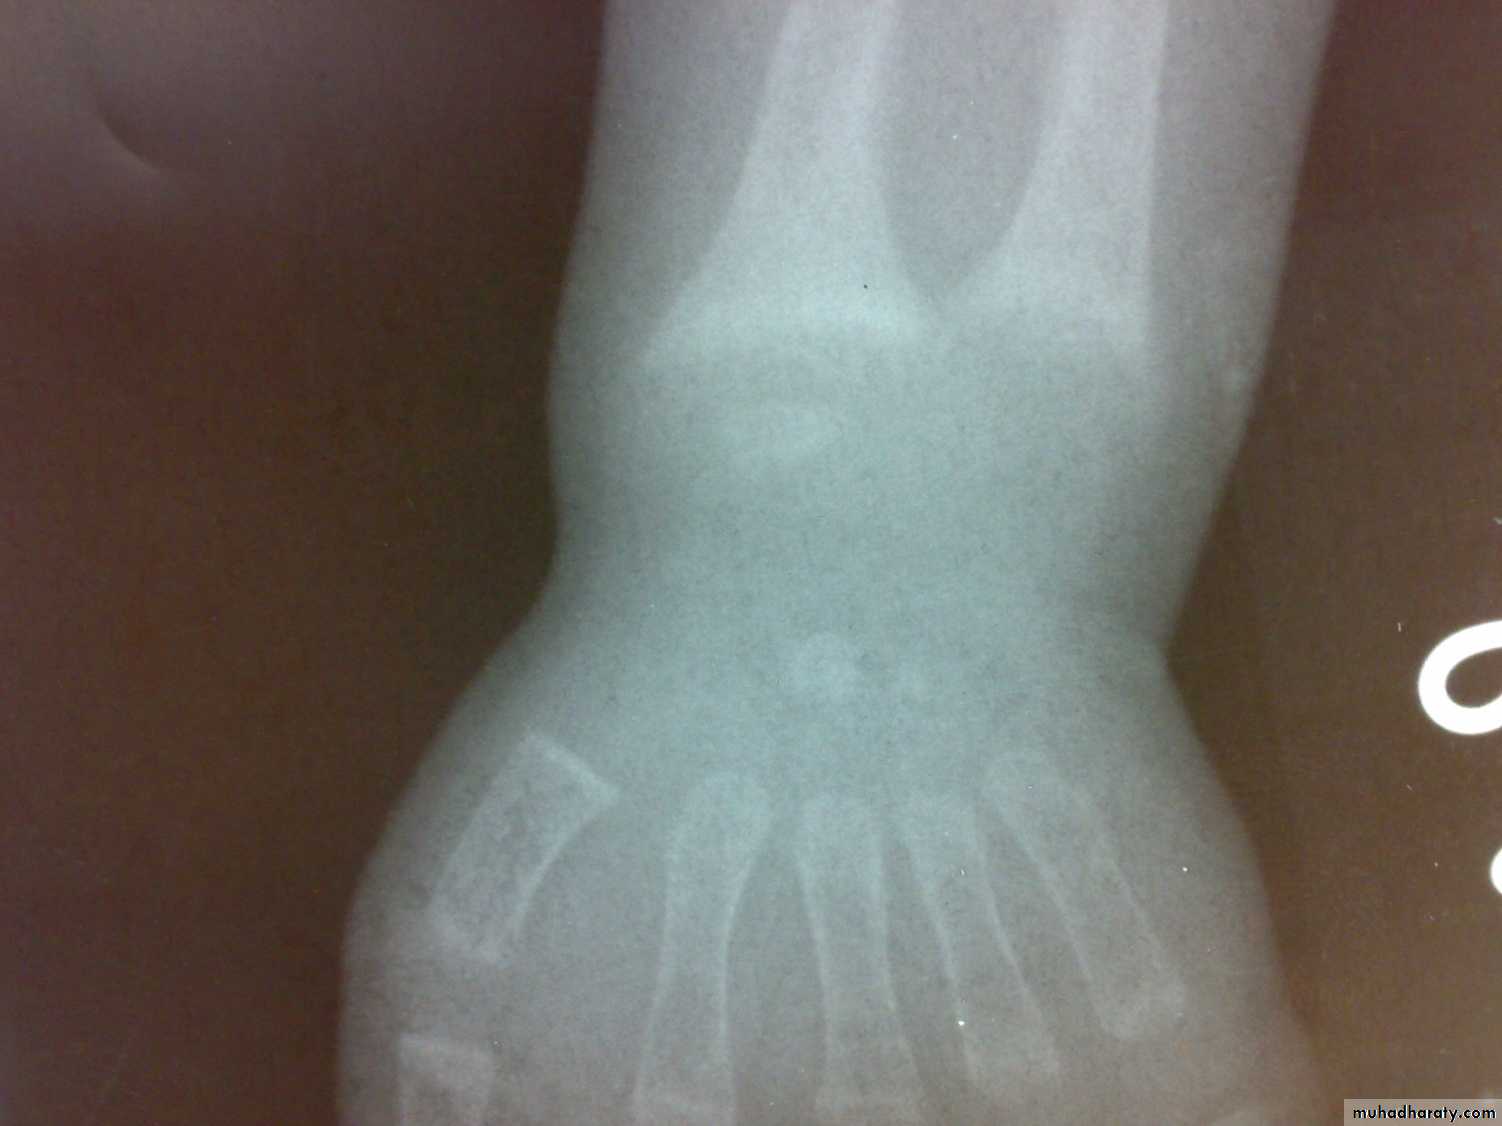

Bone tissue throughout the skeleton is abnormally less calcified and therefore soften ( Osteomalacia).Rickets and Osteomalacia is same disease.

Osteomalacia and ricketsinadequate mineralization of bone

Osteoporosis and Osteomalaciacommon in aging women, prone to pathological fractures, and decreased bone density.

Osteomalacia

Losser’s zone

decreased serum phosphate

elevated serum alka. Phosphatase.

Ca × p < 2.4 mmol/ L